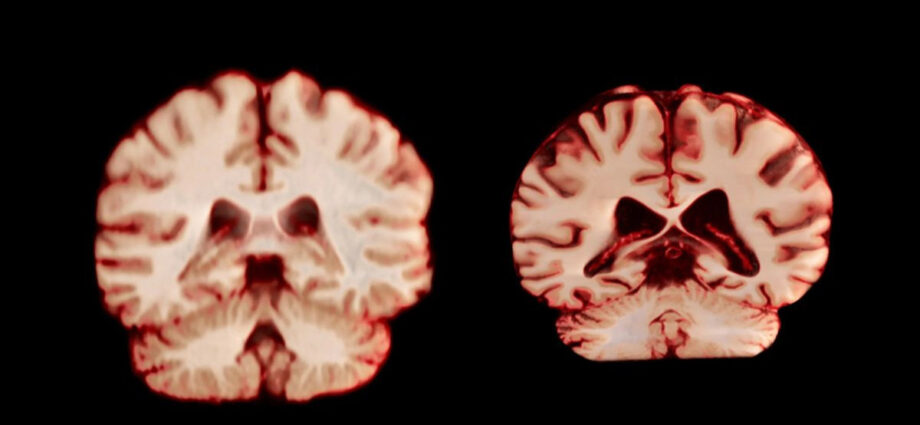

Είναι ένα από τα πιο αινιγματικά και σκληρά παράδοξα της σύγχρονης νευρολογίας. Οι γυναίκες διαγιγνώσκονται με Alzheimer σχεδόν δύο φορές συχνότερα από τους άνδρες. Για χρόνια, η επιστήμη προσπαθούσε να εξηγήσει το γιατί και η πιο διαδεδομένη υπόθεση ήταν ότι οι γυναικείοι εγκέφαλοι απλώς γερνούν ταχύτερα. Όμως, μια νέα μελέτη έρχεται να ανατρέψει τα δεδομένα: στην πραγματικότητα, ο ανδρικός εγκέφαλος φαίνεται να γερνά πιο γρήγορα και να συρρικνώνεται περισσότερο.

Η έρευνα, που δημοσιεύτηκε στο Proceedings of the National Academy of Sciences (PNAS), καταρρίπτει την παλιά θεωρία και φέρνει στο φως κάτι απρόσμενο. Οι εγκέφαλοι των ανδρών φαίνεται να υφίστανται μεγαλύτερη φθορά… Πηγή